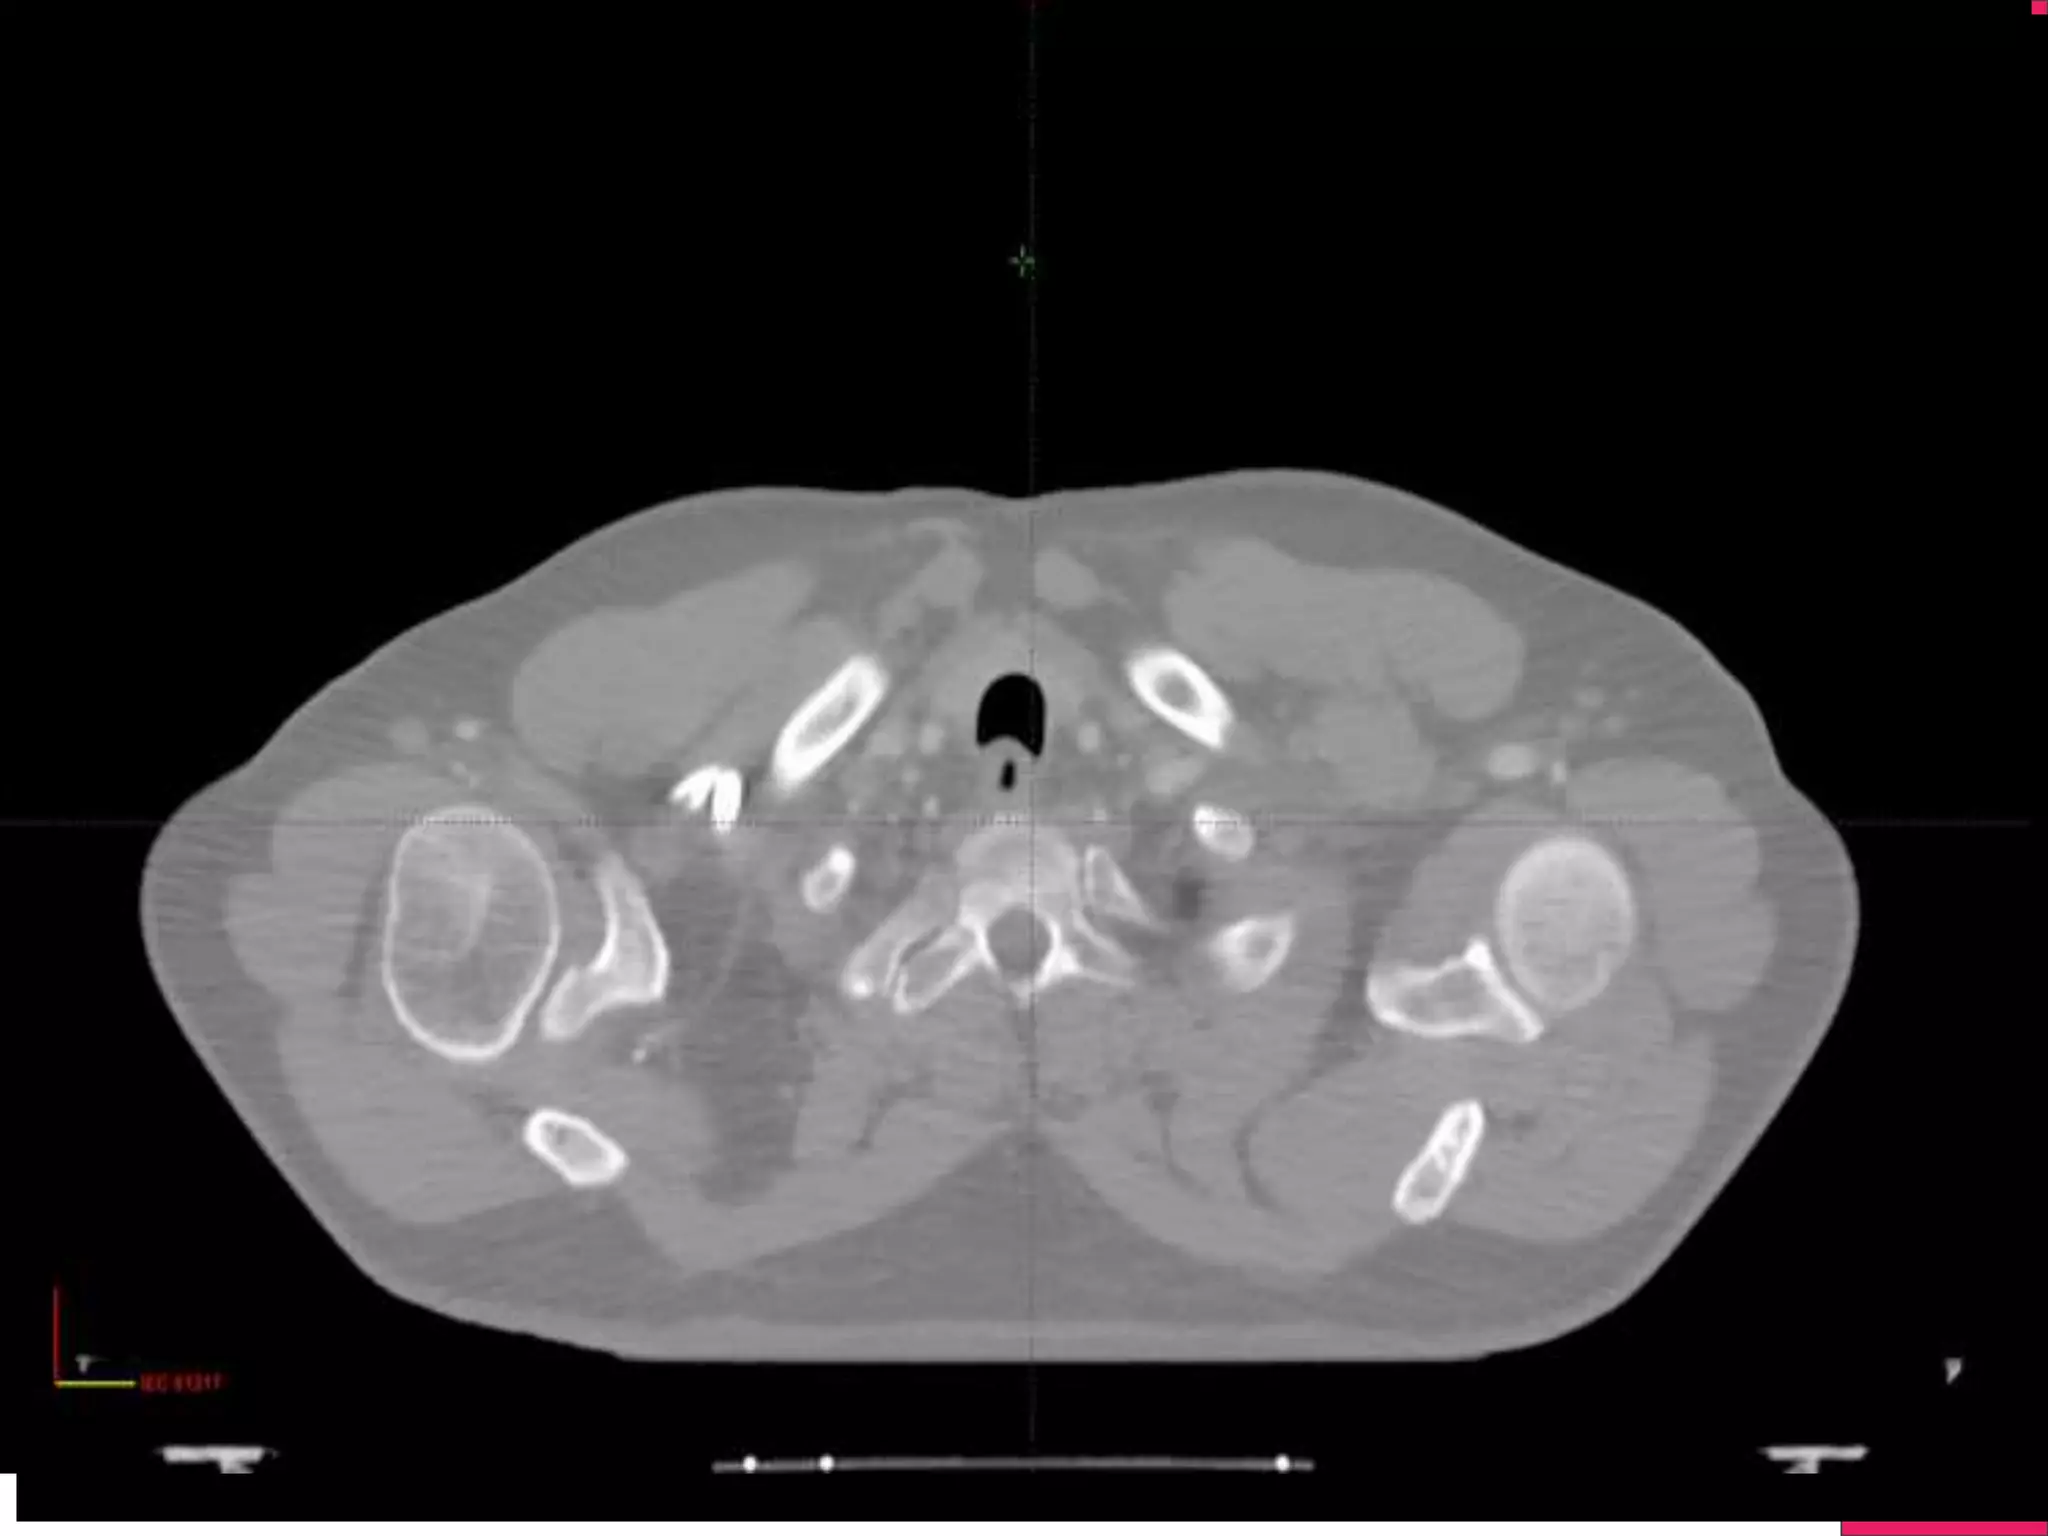

IGRT

Image Guided Radiotherapy, will use either 2D(Xray) or 3D

imaging (Cone Beam CT)

Linear Accelerators will have capability of doing a Xray and CT

Recent Development is Linac with MRI- !

Ensure the Efficiency of Treatment with the help of Imaging

Change in Anatomy can be found during treatment and corrected

IGRT Image Guided Radiotherapy,will use either 2D(Xray) or 3D imaging (Cone Beam CT) Linear Accelerators will have capability of doing a Xray and CT Recent Development is Linac with MRI- ! Ensure the Efficiency of Treatment with the help of Imaging Change in Anatomy can be found during treatment and corrected